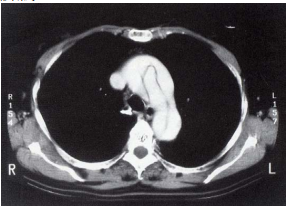

28 一位 38 歲女性,兩年前因為大腸癌做切除術,之後定期在門診追蹤。最近胸部攝影如圖 1、圖 2 所 示,病人原開刀部位無復發現象,除圖示外其它部位無異常。請就最可能的診斷選出最適當的處置: (A) 化學治療 (B)放射治療 (C)開刀切除 (D)光子刀治療

48 (A) 病人需要做化學治療 (B)病情處置以放置氣管內支架為宜 (C)病人手術切除以開胸為宜 (D)腫瘤為良性的機率較大